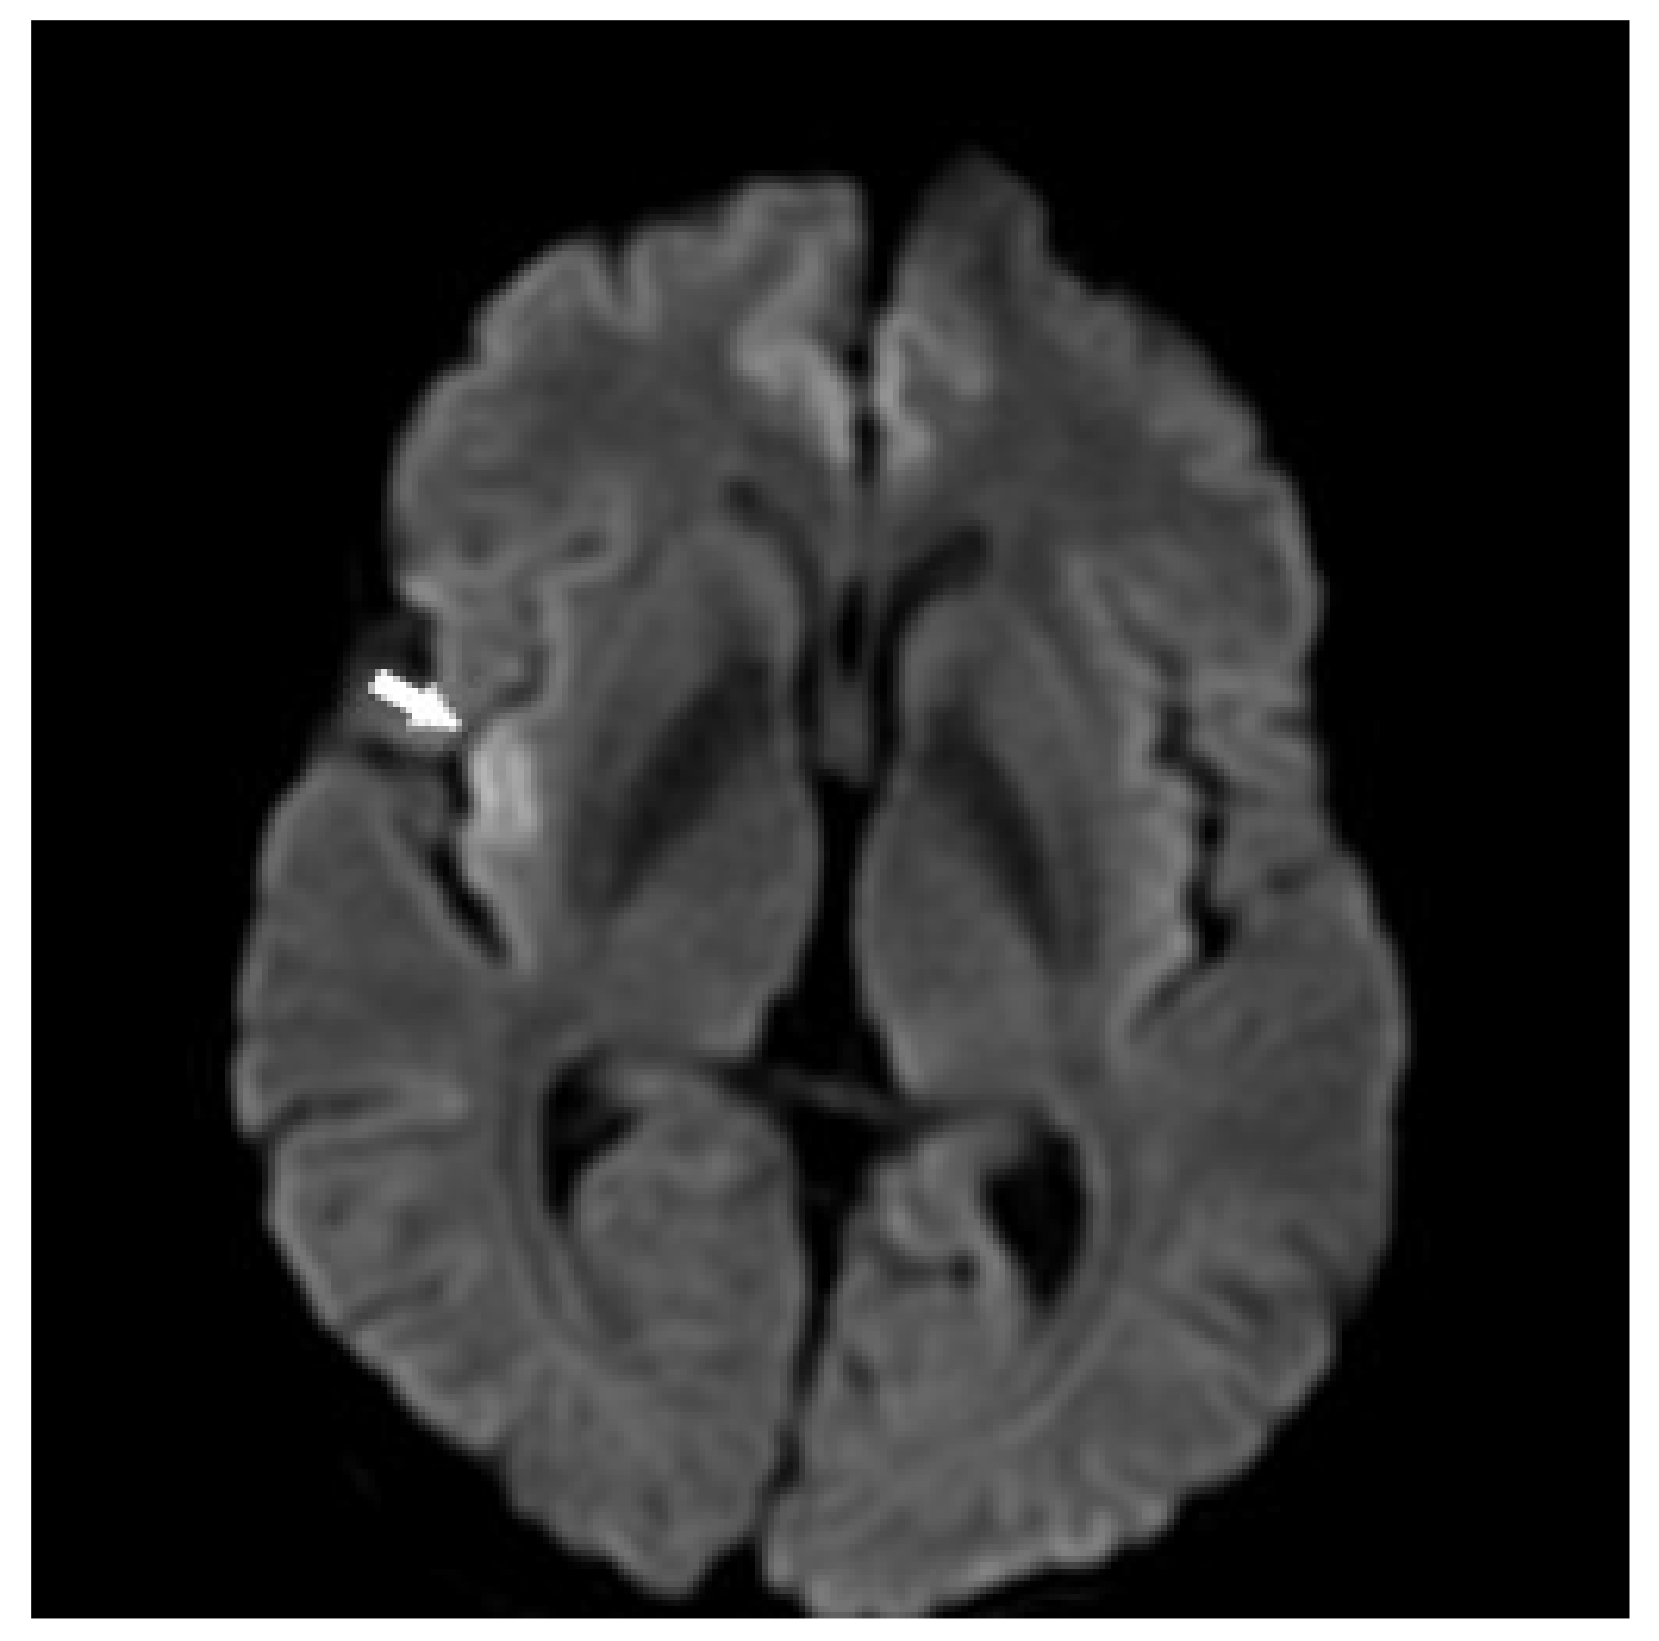

3.1. Case 1

3.3. Case 3